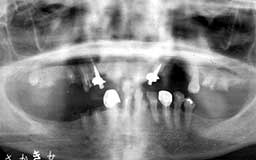

★ Uさん 38歳

当時の時代背景ということもあって、初診時38歳だったUさんのケースは少し特殊です。

メインテナンスは程度に応じて3か月・6か月・1年毎を選択するのが望ましいという保険上の

指導があったことも影響しています。多少将来が危ぶまれるものの、今すぐに何かが起こる

可能性は少ないという判断をしたUさんには3か月毎のメインテナンスを指示しました。

| Uさん 初診時 38歳 男性 歯槽骨破壊はそれほど著明ではないが、同じ年代のひとと比べれば歯槽膿漏の進行が少し 強そうな感じでした |

Uさん 20年後 57歳 長年にわたり変化のない推移だったがここ数年で急激な骨破壊を観察 |

話は戻りますが、そんななかでUさんは、唯一20年間3か月毎のメインテナンスを継続され

た貴重な存在でした。危ないから毎月に変更してもらおうと思いつつ、確実に3か月毎の予約

を守るUさんの診療態度とそれでも大きな変化もなく十分現状維持が保てている実績があって

そのままになっていました。ここ最近、左右の下顎臼歯部に急激な骨欠損が確認されたことか

ら、1か月毎のメインテナンスに切り替えることにしました。